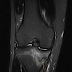

Stress Fracture MRI Losing receiver Allen Robinson for the rest of the season because of a stress fracture in his right foot is a huge blow ...